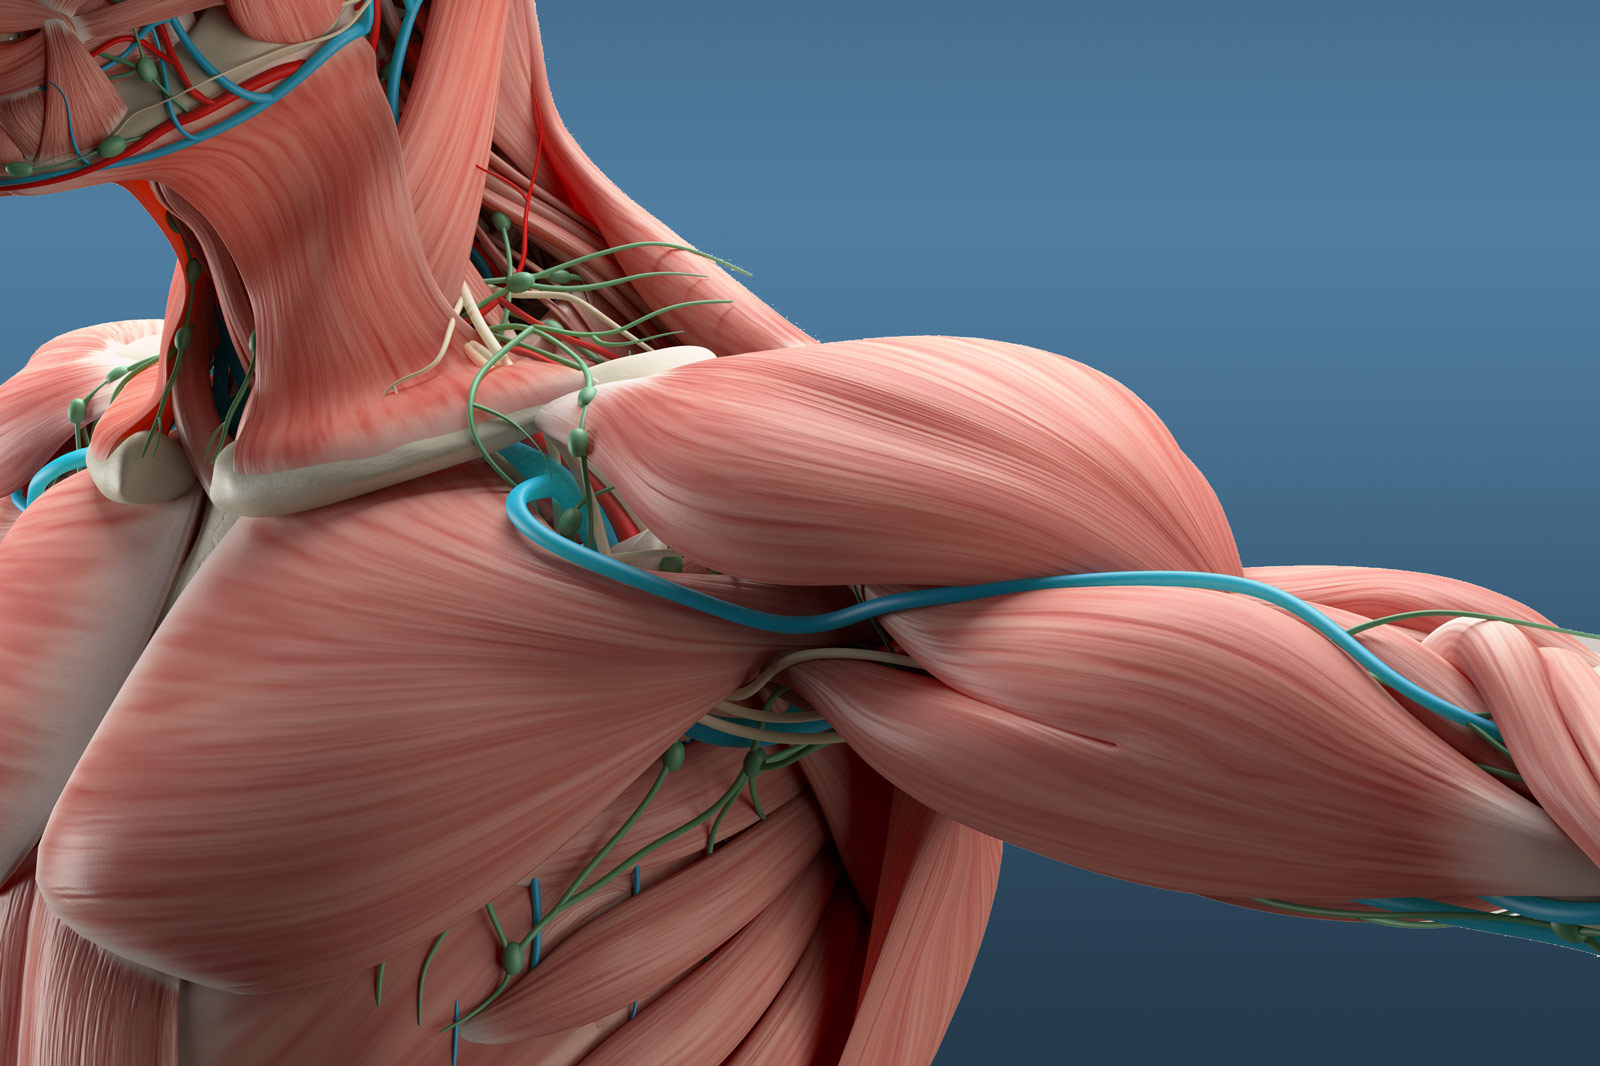

Фотографии поддельтовидной мышцы плечевого сустава